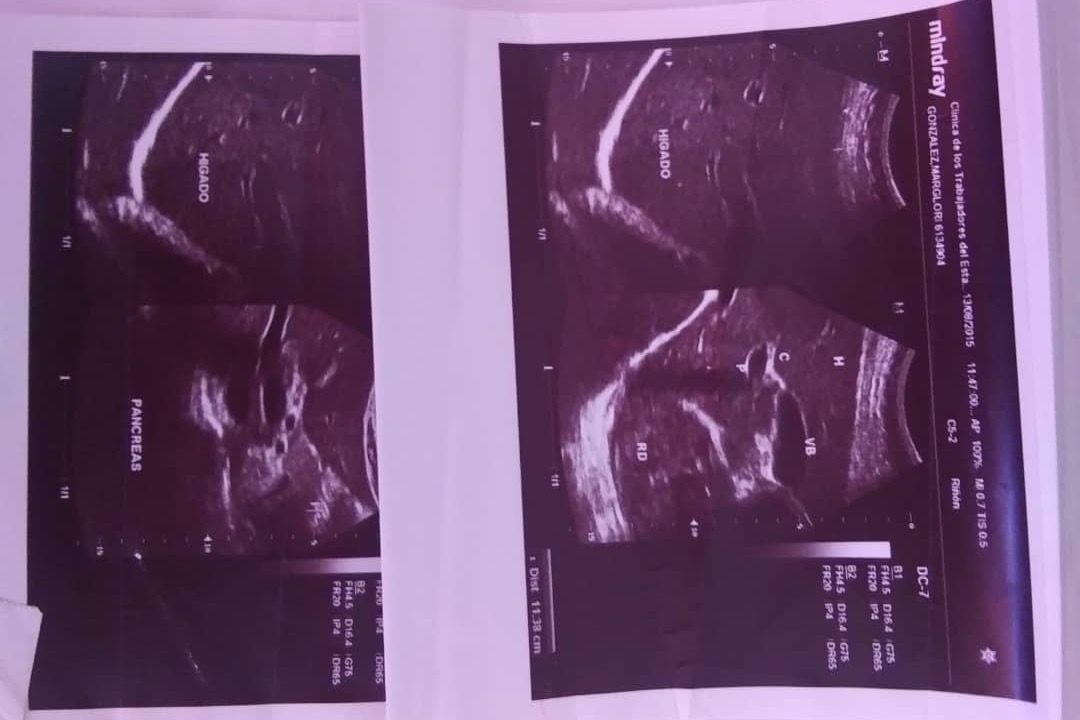

Soy un paciente con riñon único derecho.

Y me diagnosticaron quistes parapielicos derechos y pielocaliectasia derecha.

Debo ser sometida a una intervención para colocación de Catéter Doble J.